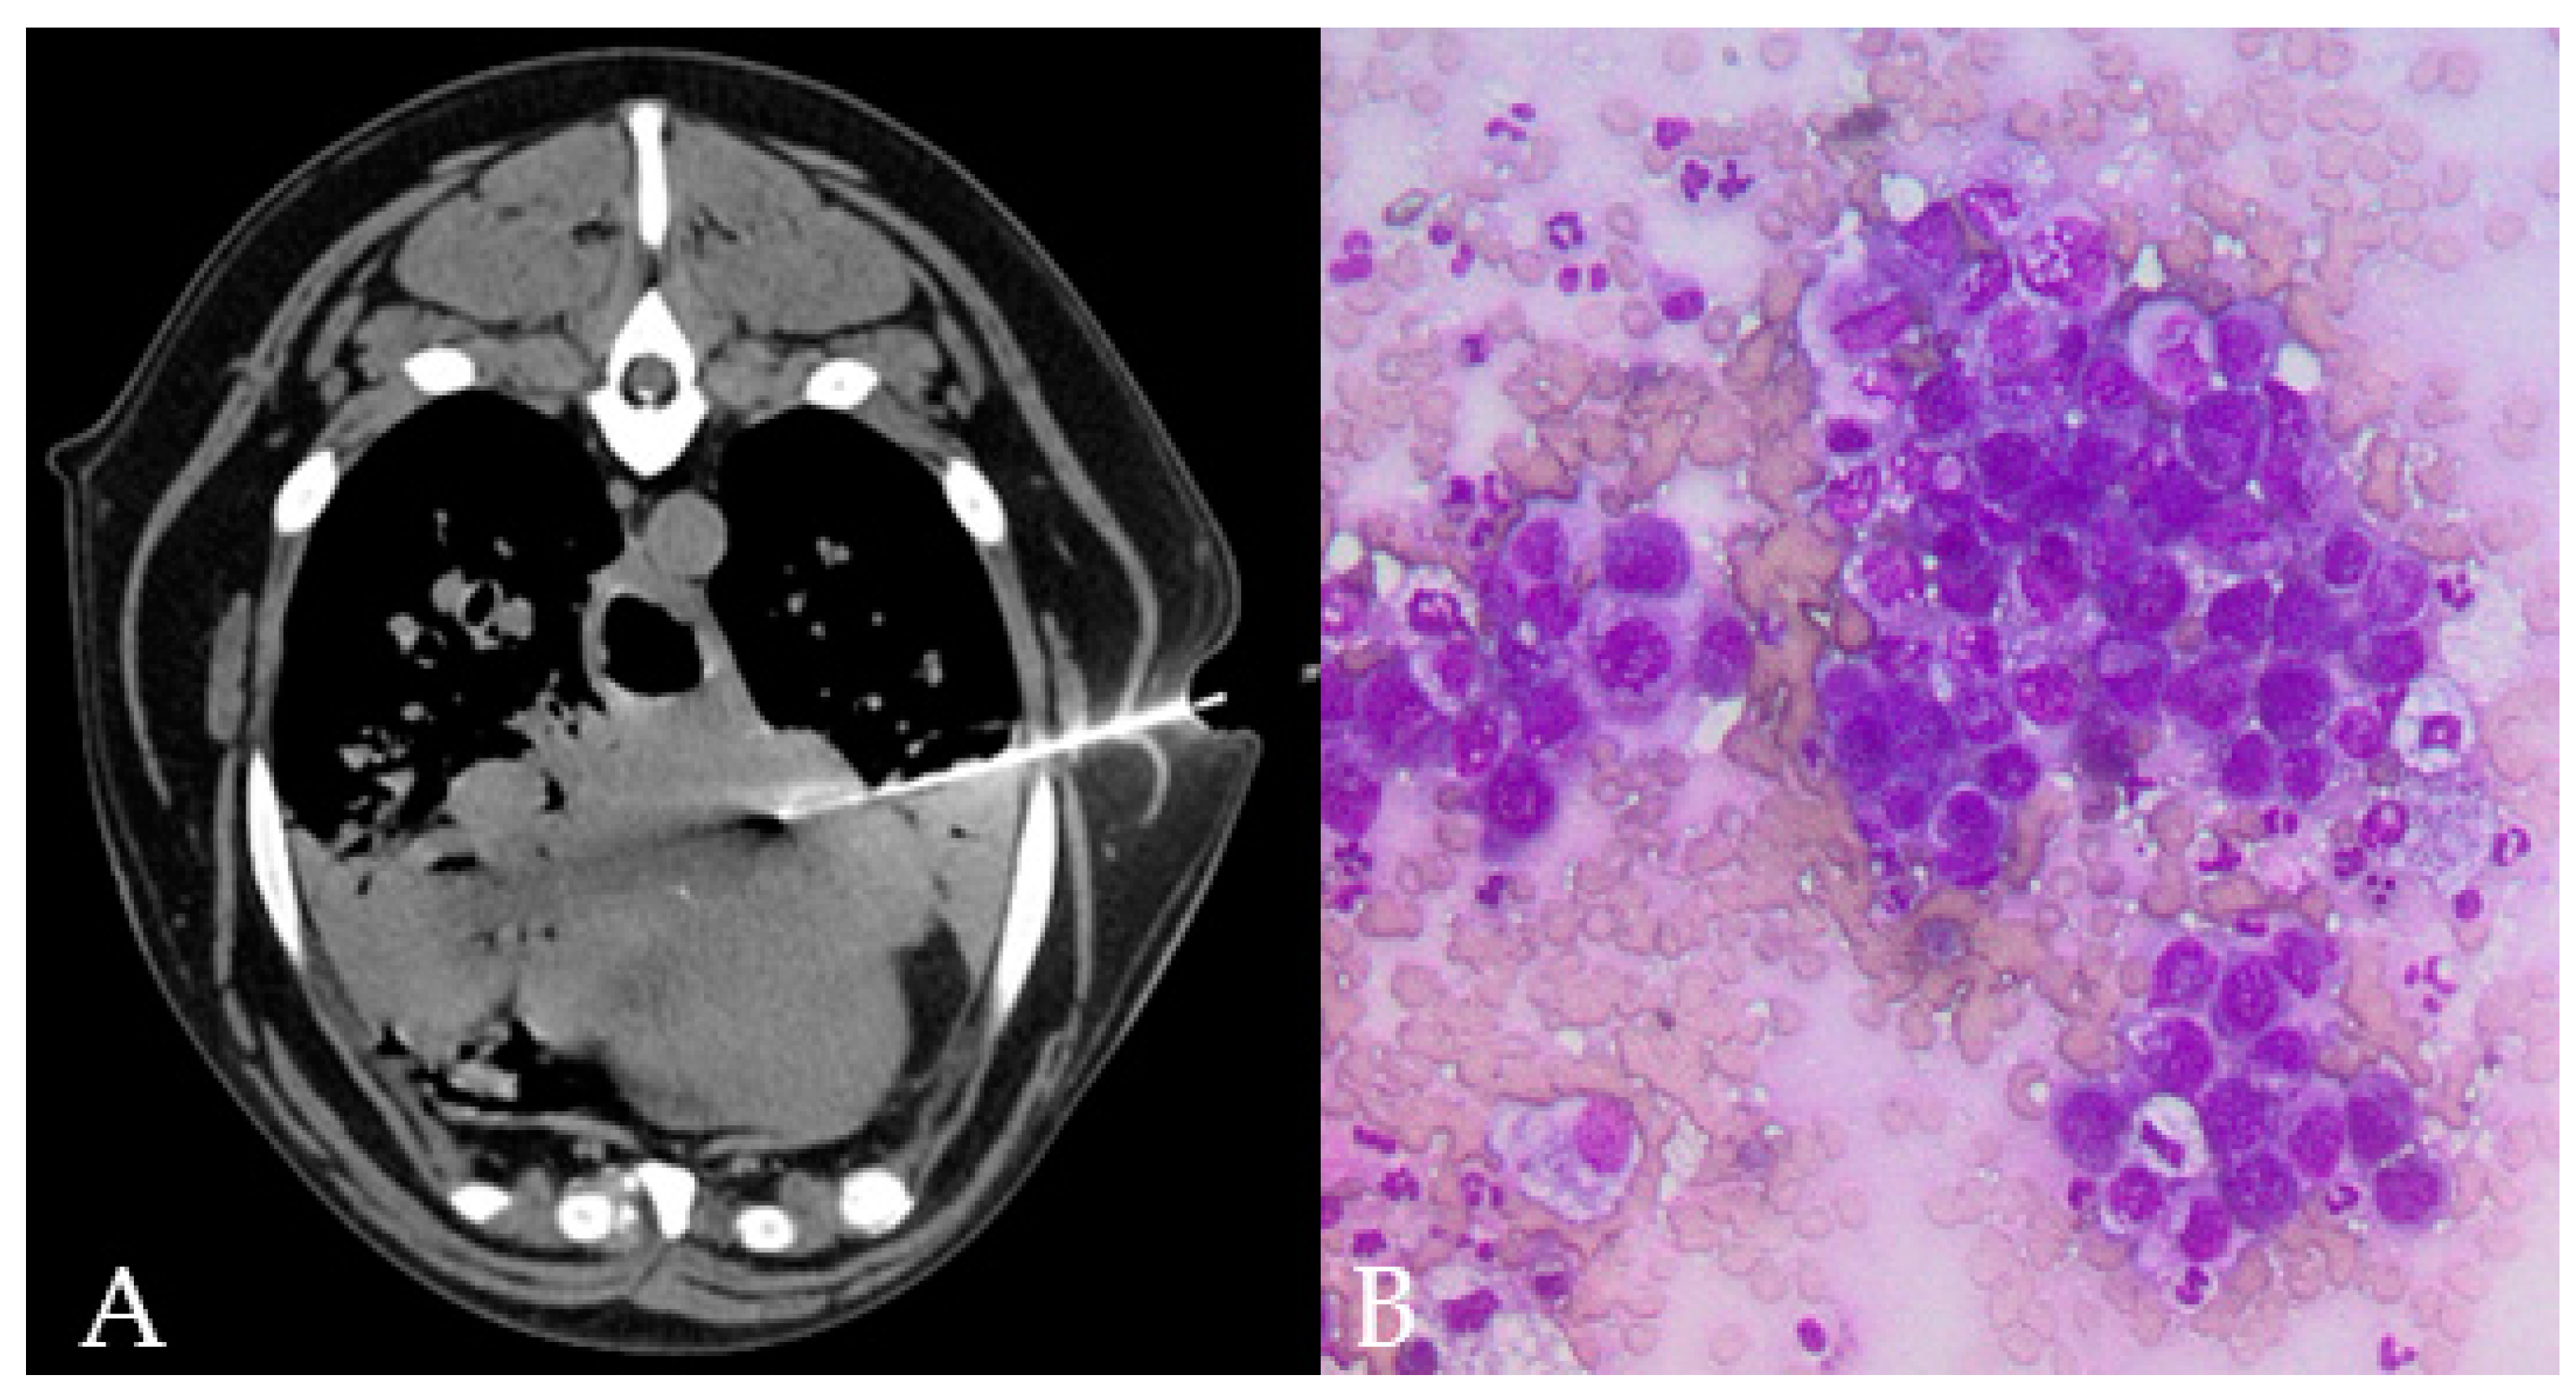

Figure 2.

(A–D) CT-guided FNAB (A) and TCB (B,C) in a cranial mediastinal mass of a dog. The automated needle was inserted through the left thoracic wall obliquely in order to avoid the rib. Cytology allowed identifying a monomorphic population of lymphoid blasts ((D) 40x magnification) in a dog with a final diagnosis of lymphoma.